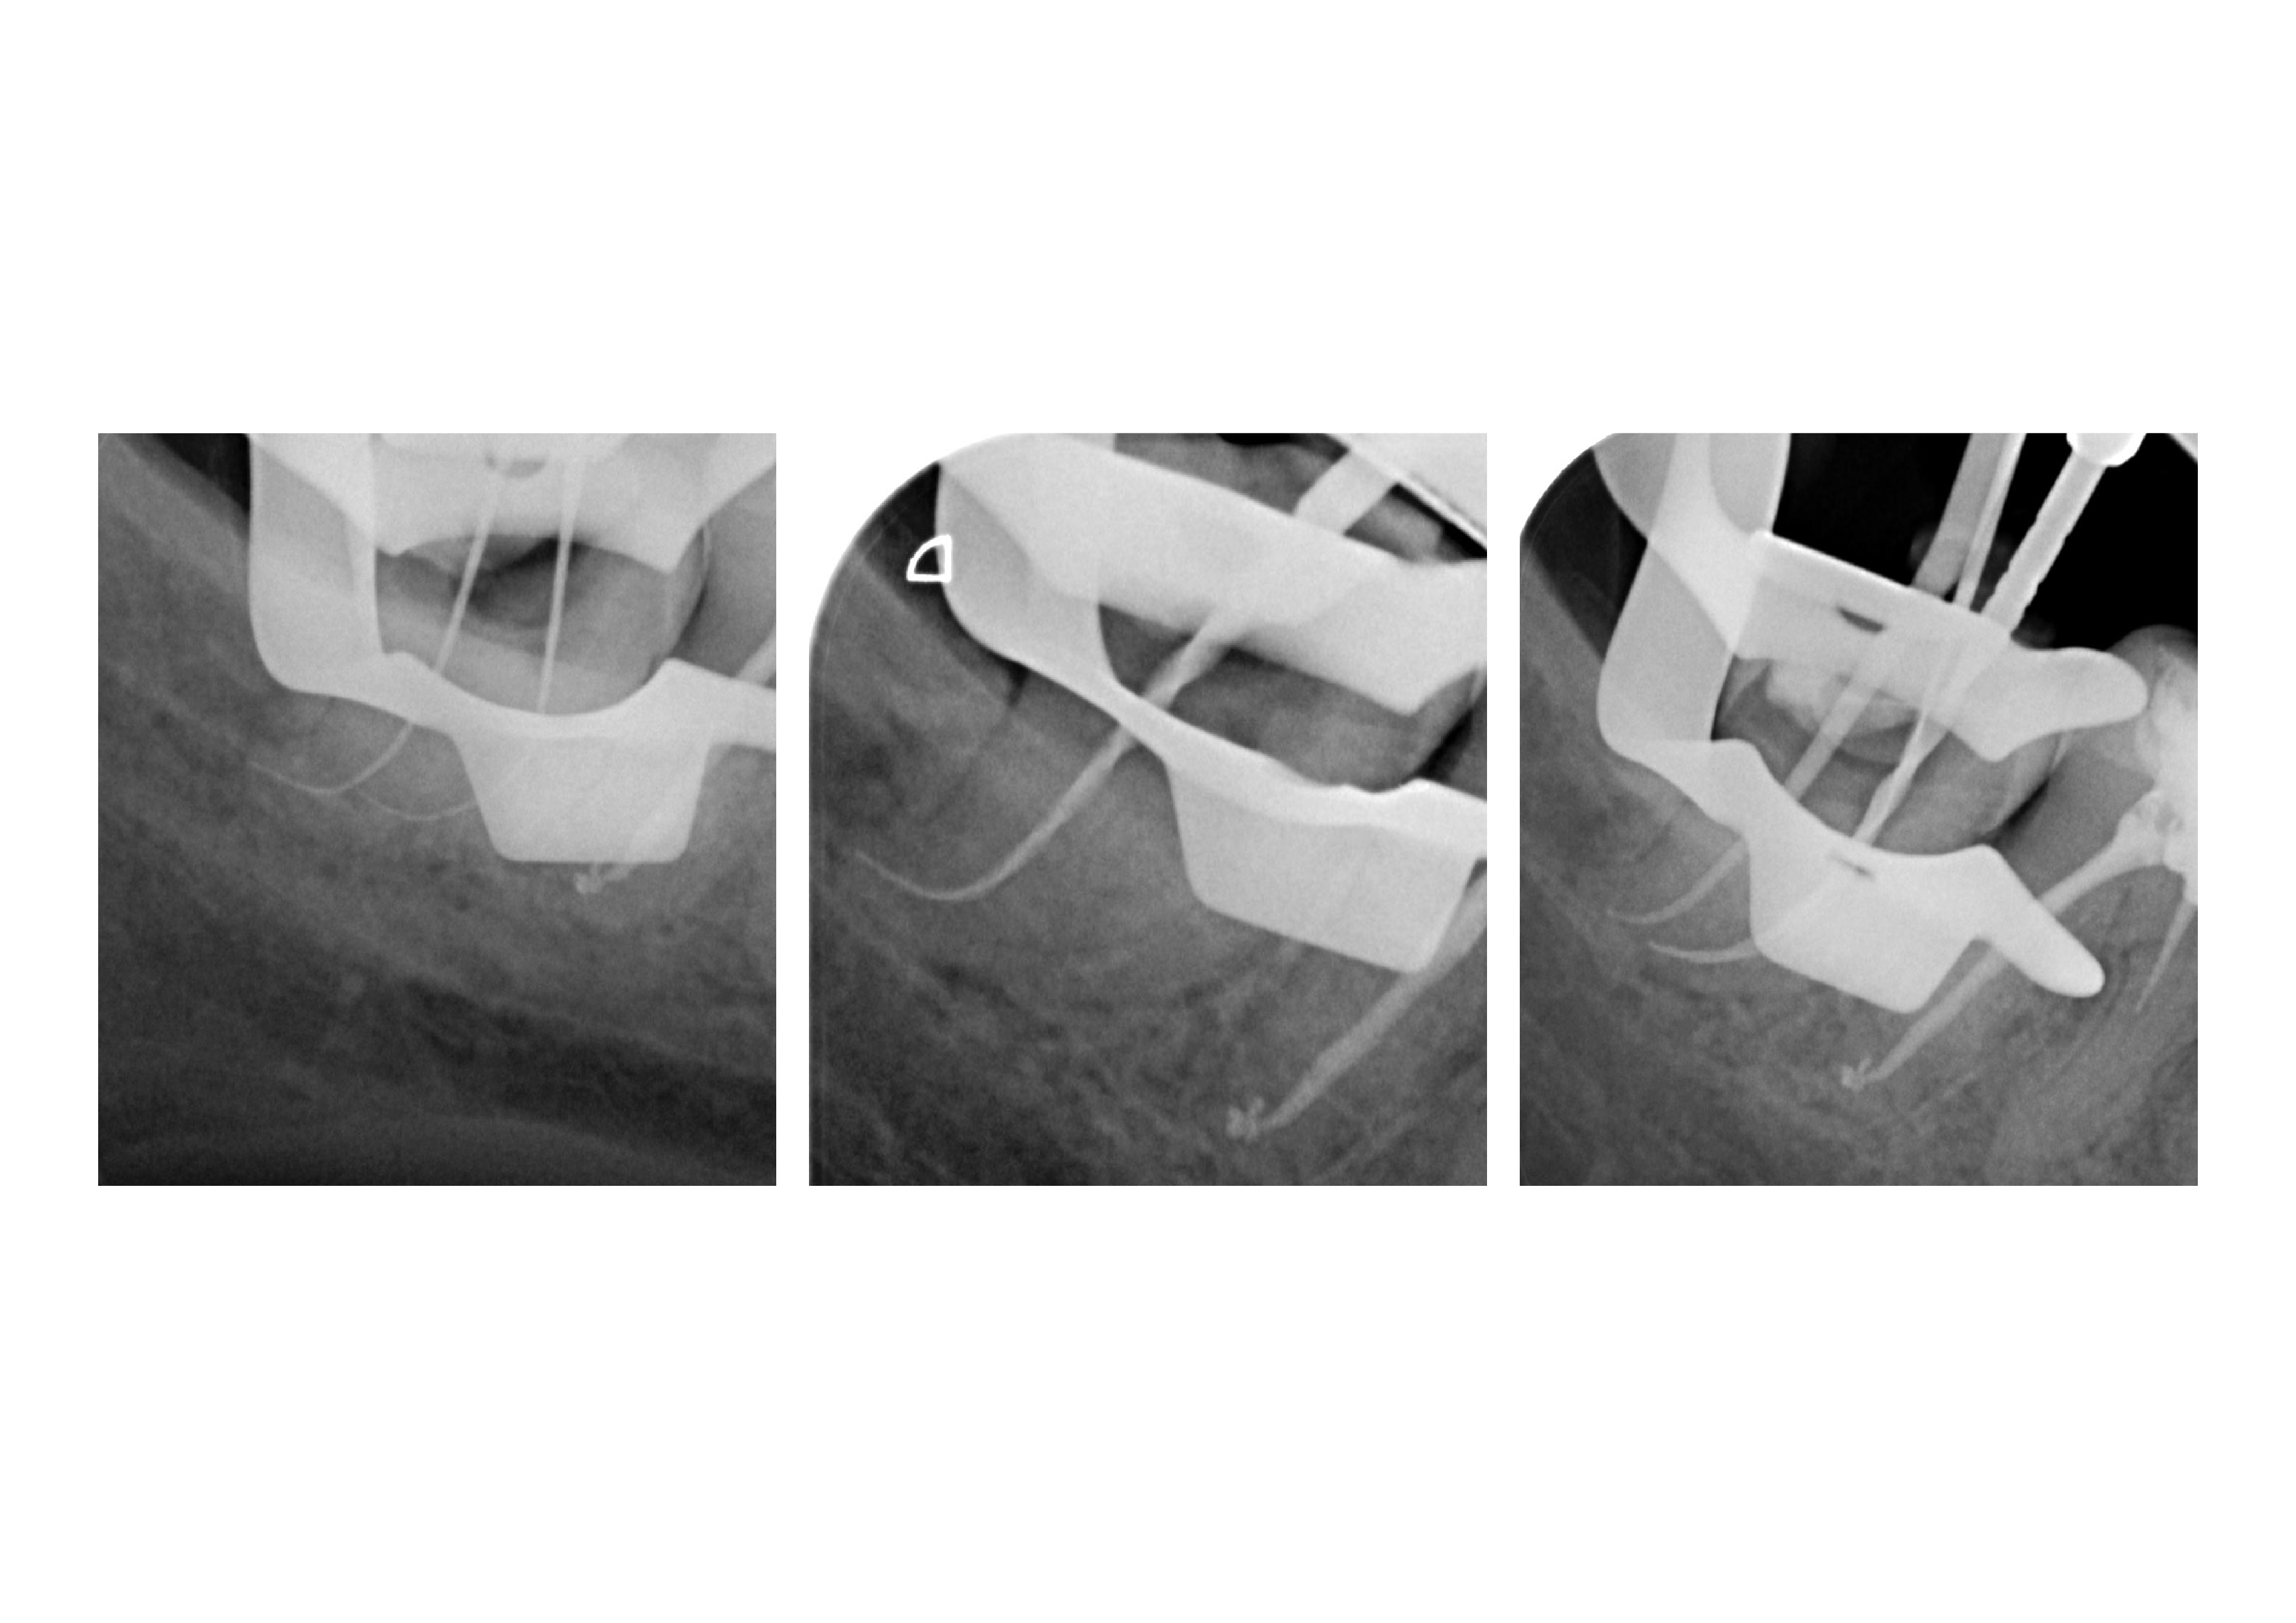

48_1 Veröffentlicht 8. Mai 2011 am 3508 × 2480 in Wurzelkanalbehandlung 48 mit RACE 02, MTwo und VDW Reciproc